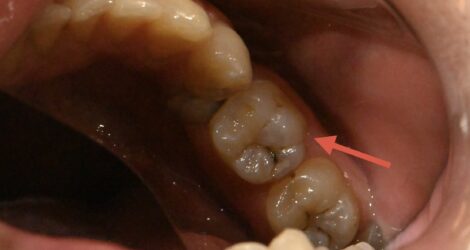

【治療前】左下第一大臼歯

MTA詰める前→詰めた後